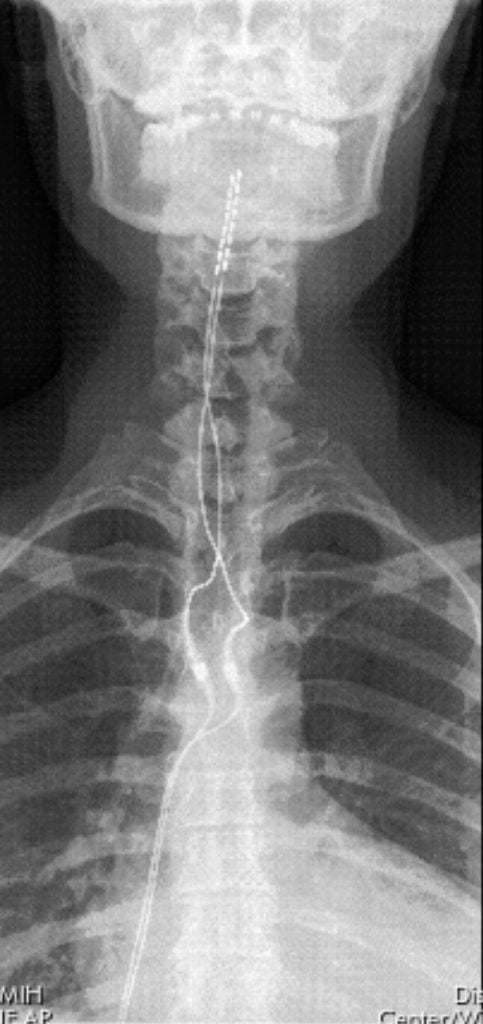

From the moment I met Dr. Gungor, I knew that he would not stop until we found an explanation for my symptoms. We first met in February 2024, where I was diagnosed with Complex Regional Pain Syndrome, type I of the right upper extremity, which is rare and permanent. During that visit, we also made a game plan of what treatments we could try to manage my condition. Dr. Gungor suggested we try another sympathetic nerve block in my thoracic spine just to see if we have a different result, if any. Unfortunately, we did not have any positive results from the second nerve block, we only had one option left - to which we referred to as the "nuclear option" - a spinal cord stimulator (SCS). Dr. Gungor explained, in great detail, what the process would be in order to get my permanent implant. He explained the risks, the potential outcomes, and his hopefulness that this option would finally bring me some relief. In August 2024, I had my SCS trial device implanted. As soon as my Boston Scientific rep (shoutout to Jared and Mike for always being amazing) dialed in my device after implantation and turned it on, the implant worked and my pain and tremor were mostly gone. I remember sitting there and crying tears of joy that something FINALLY worked for me after almost 5 years of searching for answers. In October 2024, I finally had surgery to implant my permanent SCS device. Since then, I have been able to get back to everyday activities that I once found to be exhausting and painful, and my mental health has vastly improved. I am forever grateful for Dr. Gungor's persistence, determination and kind, caring nature. Dr. Gungor has truly given me my life back. I can never thank Dr. Gungor enough for helping me manage my pain, for giving me hope, and for truly caring about my condition. Now I have a cool story to tell my students about essentially being a robot now! Thank you Dr. Gungor!